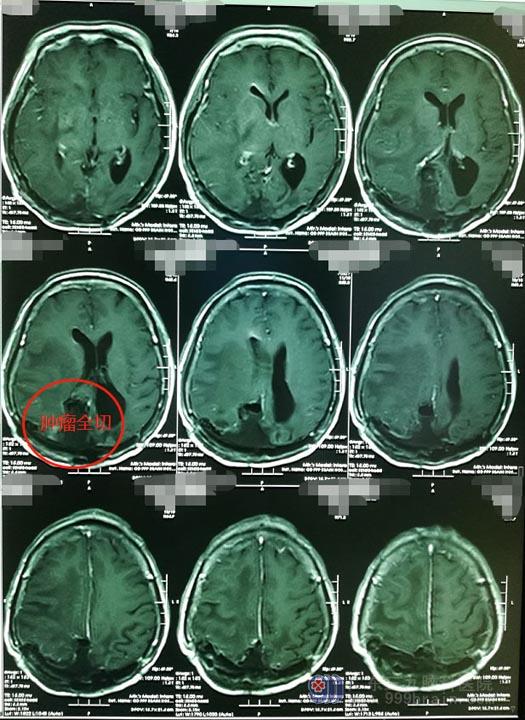

详细讲解后,钟女士和家人都决定再次手术。由鲁明主刀,术中发现肿瘤的复杂程度超过了术前的想象,经过神经外五科手术团队的共同努力,肿瘤得以顺利全切。

术后,钟女士的肢体活动得到了恢复,可以自行行走,双眼视力、视野也得到了明显的改善,已经可以看到门外的东西了。她老公告诉医生:妻子感觉这次手术比之前的3次都轻松很多,没有太多的难受,恢复得也非常快。